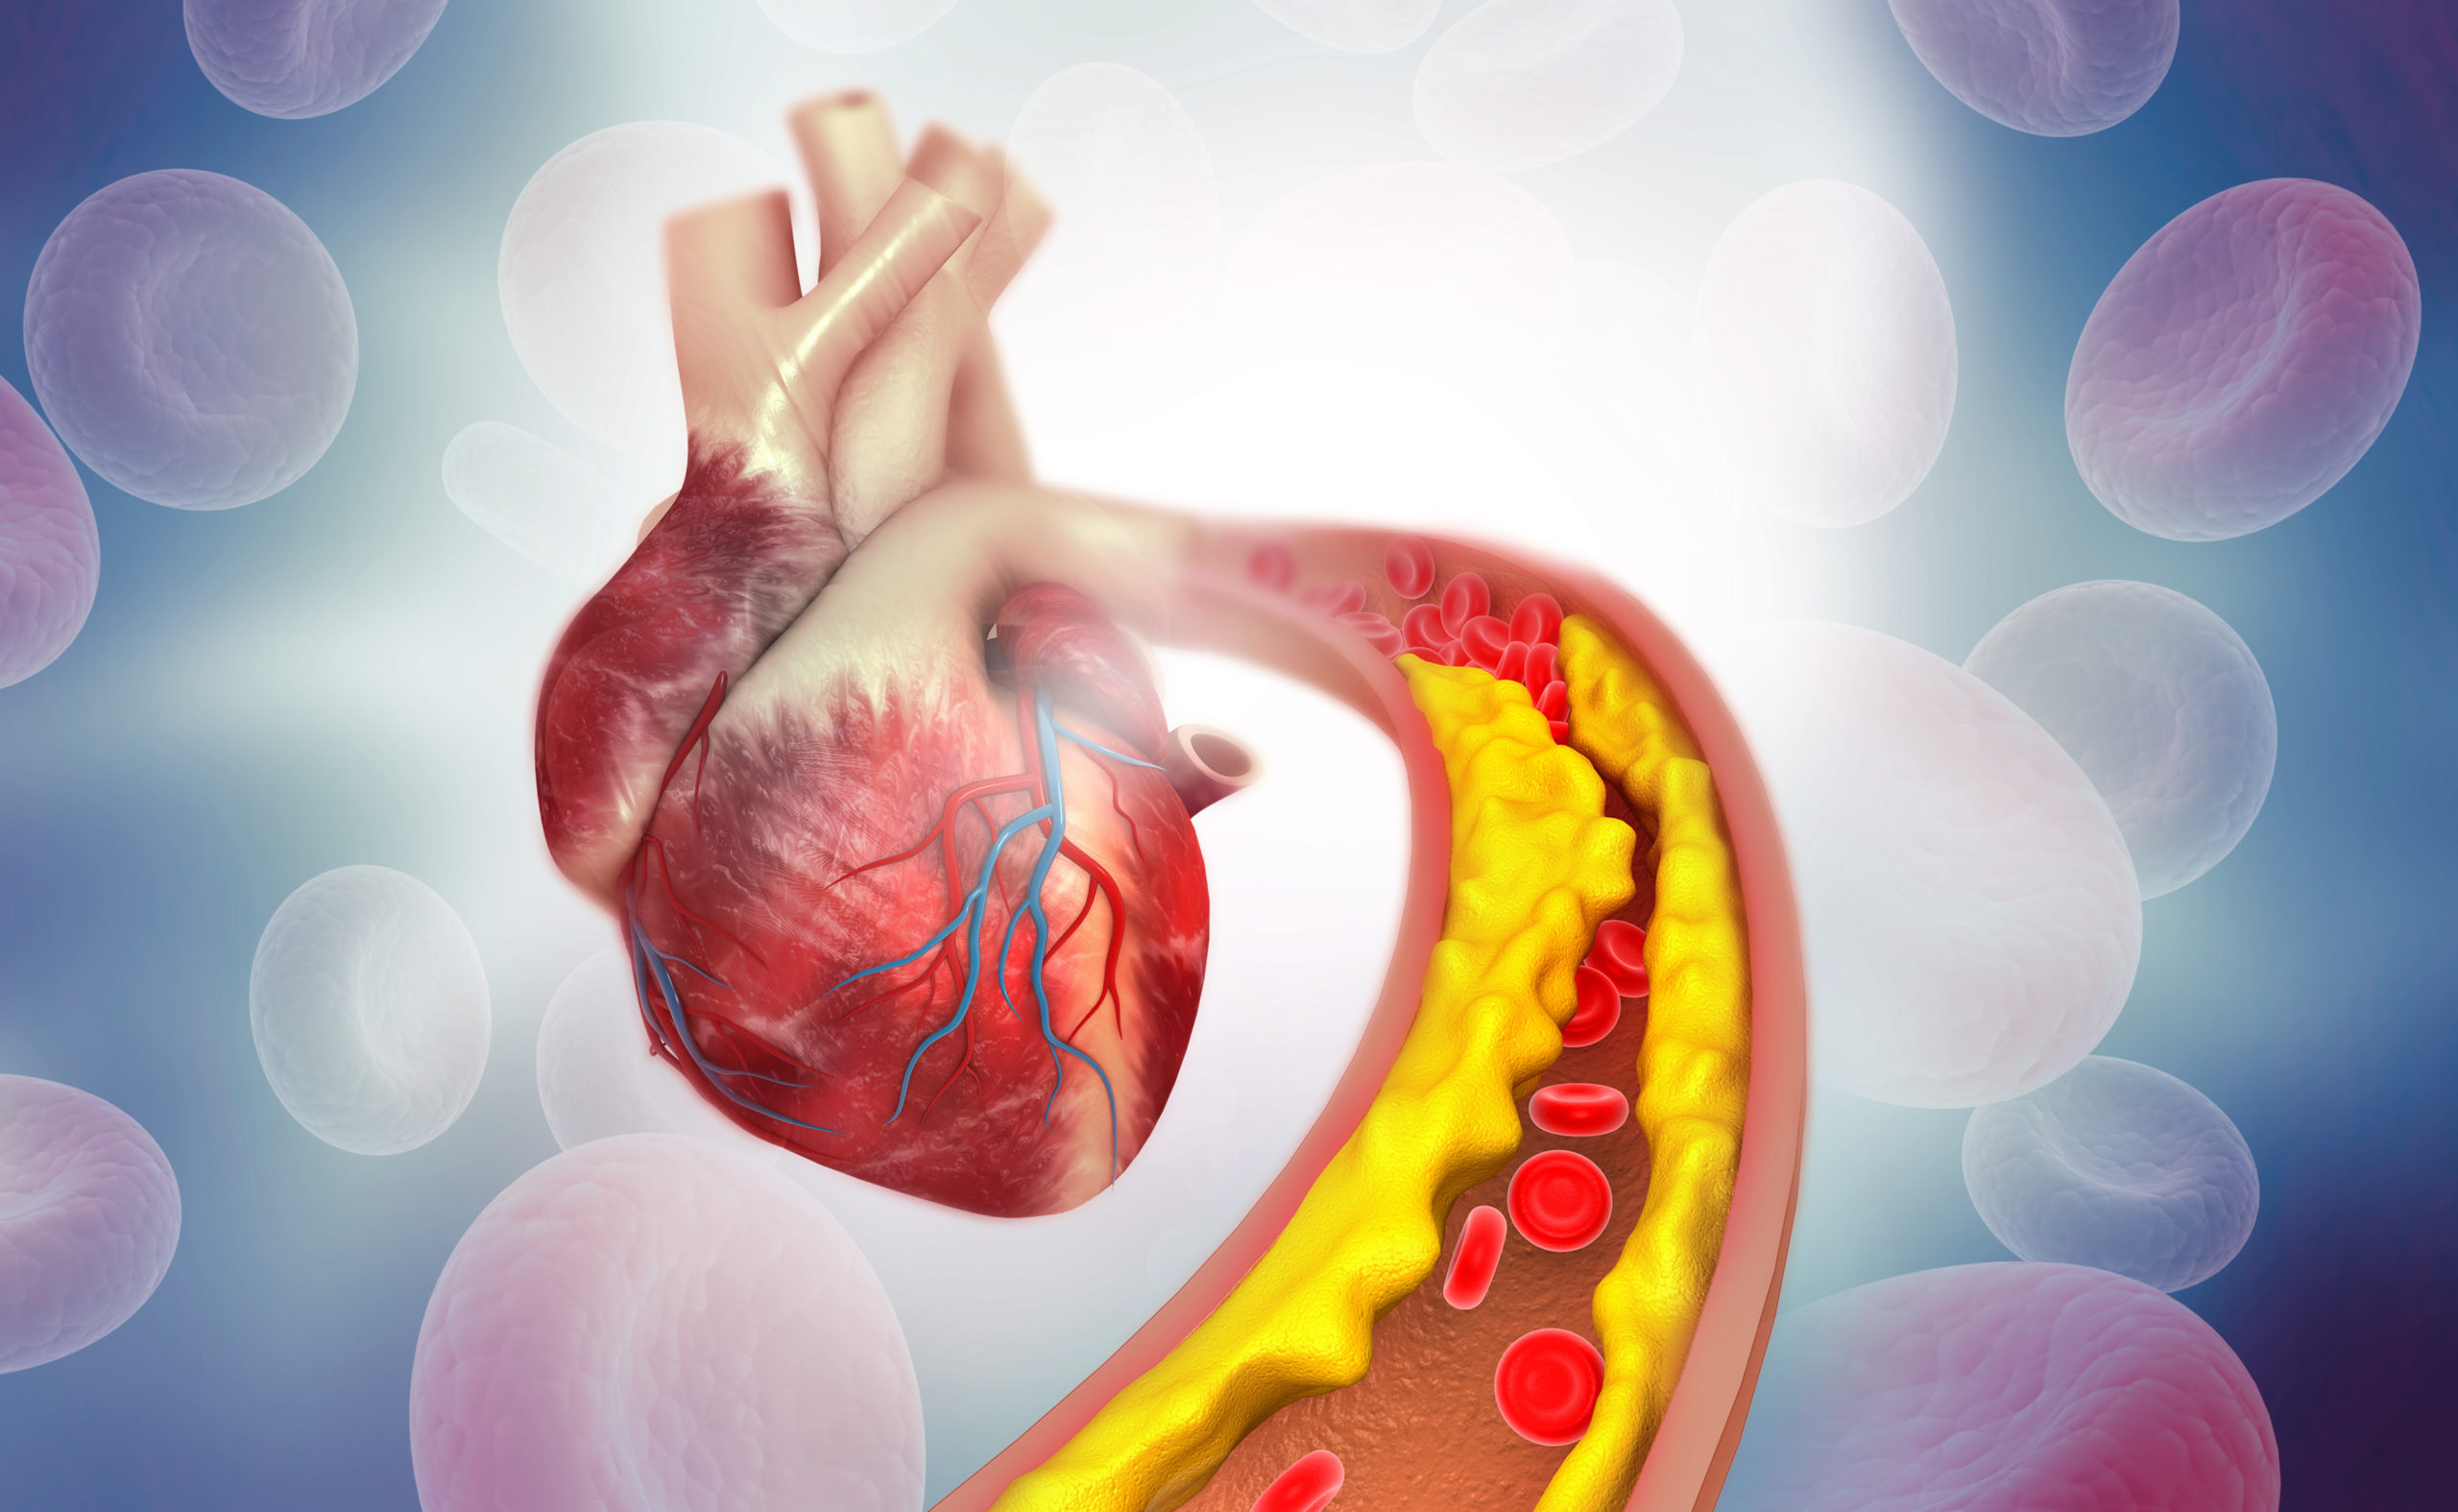

coronary artery disease

In patients with atrial fibrillation and coronary artery disease (CAD), researchers found that rivaroxaban monotherapy ...

In a recent study, published in BMC Cardiovascular Disorders, researchers evaluated the role of HOMER1, ...

A pooled analysis of randomized trials found that moderate to severe coronary artery calcification (CAC) is associated ...

Coronary computed tomography angiography (CCTA) can detect atherosclerosis, even among individuals with no coronary ...

The results of a study show a link between the profile of serum fatty acids (FAs) and early-onset coronary artery ...